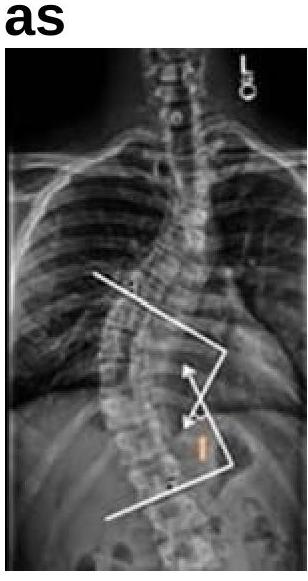

What is the angle shown in the image known as?